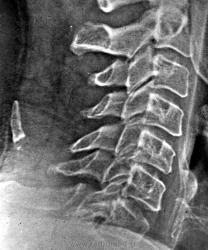

Стандарт исследования при травме предполагает минимум 2 проекции. По локализации костного фрагмента и его форме можно предположить отрывной перелом одного из остистых отростков. Не люблю гадать на кофейной гуще. Прямая пр. должна поставить все на свои места.

К сожалению в архиве единственный снимок, помню, что в прямой проекции тень вообще не была видна - располагалась срединно и сливалась с остистыми отростками.

У многоуважаемого проф. Королюка И.П., это состояние обозначено как "объызвествление выйной связки"-на самом деле, это конечно оссификация( плотность извести и кости разная)-метаплазия мягких тканей в кость по С.А. Рейнбергу.

А не откололась-ли эта "чертовина" от остистого отростка?

Нет подходящего материнского фрагмента...

Я такое уже видела, что-то обызвествилось.

Вот, точно, так они и называются. В атласе Королюка написано просто обызвествление выйной связки.

Спасибо за Дьяченко! Супер, и никаких обид! Но как красив, гаденыш - просто-таки фрагмент остистого!

А может быть действительно "фрагмент", а рядом маленький "фрагментик"?